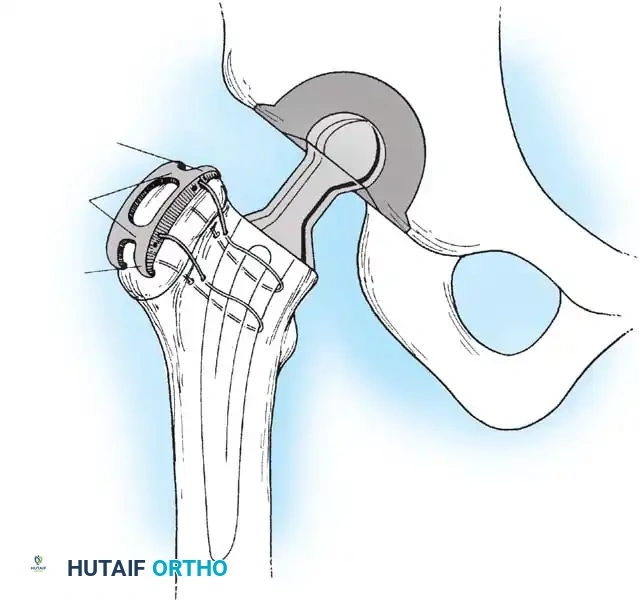

Image

1. Component Insertion: Impact the trial shell to confirm stability and coverage. Once confirmed, impact the final porous-coated (uncemented) acetabular shell. Ensure a rigid press-fit. Supplemental screws may be used in the safe zone (posterosuperior quadrant) if initial stability is questionable.

FEMORAL PREPARATION AND IMPLANTATION

Deliver the proximal femur into the wound by extending, adducting, and internally rotating the leg. Place a retractor under the calcar to elevate the femur.

1. Canal Preparation: Use a box osteotome to remove the lateral cortical bone of the femoral neck, ensuring straight-line access to the diaphysis. Use a canal finder or T-handled awl to open the medullary canal.

2. Broaching: Sequentially broach the femur, starting with the smallest size. Ensure the broach is in neutral alignment (avoiding varus). Advance the broaches until rotational stability is achieved and the broach fills the metaphyseal envelope.